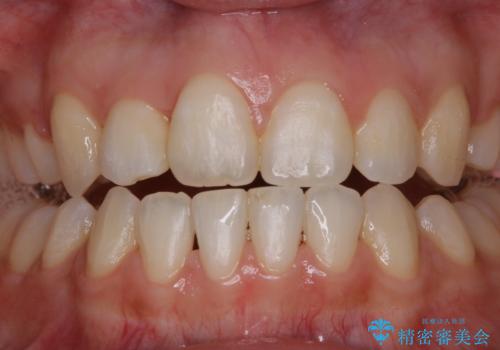

ホワイトニング 1日で真っ白な歯に

- ホワイトニングで歯を白くしたいとのことでした。

処置前クリーニング¥3300・オフィスホワイトニングのエクセレントコース¥29700を行いました。

- ¥33000費用は治療当時の料金となります